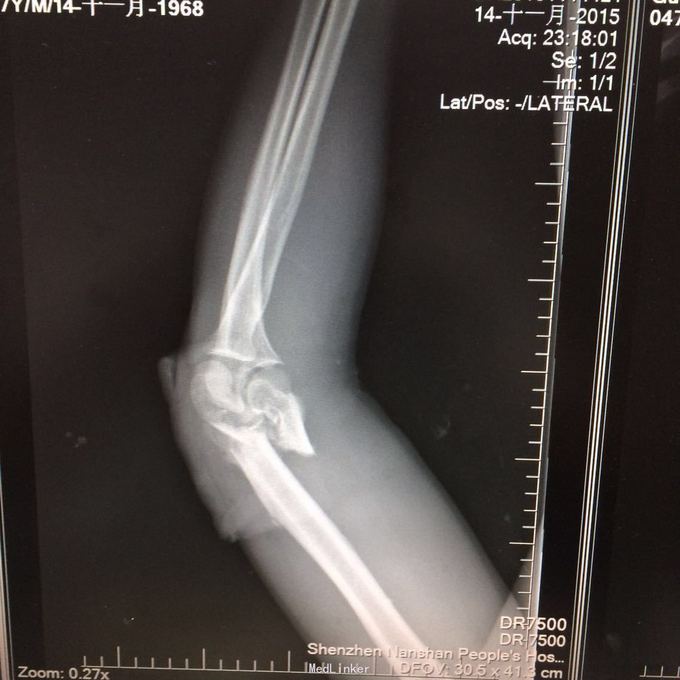

患者某某,男,49岁,因“高处坠落致全身多处疼痛、肿胀、流血2小时 1、男性壮年患者。 2、缘患者于2小时前因高处坠落致左肘、左手、右手、头面部、左胸,左足等多处受伤,即觉左肘部疼痛、活动困难、流血;左手、头面部伤口疼痛、流血;右手、左胸,左足部等处疼痛、肿胀。由家属、同事送往我院就诊,经行X线检查示:左肱骨远端粉碎性骨折,左肘关节半脱位;左手第4、5掌骨远端骨折;右手第1远节指骨基底部、第3、4远节指骨骨折,第5中节、远节指骨骨折;左跟骨粉碎性骨折。CT示:鼻中隔骨折;右侧第3--7肋骨折。急诊科予清创包扎止血,为作进一步诊治而收入院。患者受伤以来,患者精神好,无呼吸困难,无恶心、呕吐,无头晕,无面色苍白,无双下肢麻木、无力,无大小便失禁。 3、查体:T36.8 ℃ P 76次/分 R20 次/分 BP104/67mmHg。神清合作、应答切题、全身皮肤粘膜无黄染、浅表淋巴结无肿大。头颅五官无畸形,左眉弓处见一长约2cm伤口,活动性出血,巩膜无黄染,双侧瞳孔等大等圆,直径 3 mm,对光反射灵敏。鼻梁有一长约3cm纵行伤,深及皮下,伴有活动性出血;下唇部见一1*1cm组织缺损,伴活动性出血.颈软,无抵抗,气管居中,甲状腺无肿大,胸廓无畸形,右侧胸部局部压痛明显,胸廓挤压征阳性;心前区无隆起,双肺叩诊清音,呼吸音清,无干湿性罗音。心率76次/分,律齐有力,各瓣膜区无病理性杂音。腹平,腹肌软,全腹压痛、无反跳痛,肝脾肋下未及,双肾区无叩痛,无移动性浊音,肠鸣音存在,4-6次/分。脊柱、骨盆无压痛,四肢检查详见专科情况,其余肢体检查正常。双下肢生理反射存在,病理性反射未引出。

4、专科情况:左肘部中度肿胀,呈短缩、成角畸形,局部皮肤活动性出血,局部压痛明显,纵向叩击痛,左肘部可扪及骨擦感,有反常活动,左肘部活动障碍。左肩峰至肱骨外上髁上臂长度较右侧短缩1厘米,左手掌尺侧轻度肿胀,无畸形,局部皮肤正常,局部压痛明显,可扪及骨擦感,无反常活动,左手指活动正常。左侧手指肌力Ⅳ级,有牵拉痛,左上肢手指末梢血运良好,感觉略差。右手拇指、环指及尾指局部皮肤组织撕脱,渗血明显;右手中指末端损毁,局部缺失。右手手指肌力Ⅳ级末梢血运良好。左足跟部肿胀明显,局部皮肤正常,局部压痛明显,纵向叩击痛,左足跟部可扪及骨擦感,左足趾肌力Ⅳ级,无牵拉痛,左足趾末梢血运及感觉良好。 5、辅助检查:本院2015年11月14日X线检查示:左肱骨远端粉碎性骨折,左肘关节半脱位;左手第4、5掌骨远端骨折;右手第1远节指骨基底部、第3、4远节指骨骨折,第5中节、远节指骨骨折;左跟骨粉碎性骨折。CT示:鼻中隔骨折;右侧第3--7肋骨折;左下肺挫伤。

1、左肱骨远端粉碎性开放性骨折;2、左肘关节半脱位;3、左手第4、5掌骨远端骨折;4、右手第1、3、4远节指骨骨折;5、右手第5中节、远节指骨骨折;6、鼻部软组织挫裂伤;鼻中隔骨折;7、右侧第3--7肋骨折;8、左跟骨粉碎性骨折;9、左眉弓软质挫裂伤;10、左肺挫伤;11、脑震荡。 1.完善三大常规、PT四项、生化等各项常规检查; 2.完善CT检查,予抗破伤风、抗感染、镇痛、止血等对症支持治疗; 3.请口腔、耳鼻喉、眼科等相关科室会诊; 4.请示上级医师,指导下步治疗。 手术时间:2015年11月15日 术后诊断:左肱骨远端开放性粉碎性骨折 麻醉方式:全身麻醉 手术名称:左肱骨远端开放性粉碎性骨折清创缝合外固定架固定术 手术时间:2015年12月25日 术后诊断:左肱骨远端粉碎性骨折 麻醉方式:臂丛麻醉 手术名称:左肱骨远端粉碎性骨折切开复位内固定术 。 手术时间:2015-12-3 术后诊断:左跟骨粉碎性骨折;左肱骨远端粉碎性开放性骨折;左肘关节半脱位;左手第4、5掌骨远端骨折;右手第1、3、4远节指骨骨折;右手第5中节、远节指骨骨折;右足拇趾撕脱骨折并趾间关节脱位;鼻部软组织挫裂伤;鼻中隔骨折;右侧第3--7肋骨折;左眉弓挫裂伤;左肺挫伤;脑震荡。 麻醉方式:腰硬联合 手术名称:左跟骨粉碎性骨折切开复位钛板内固定术